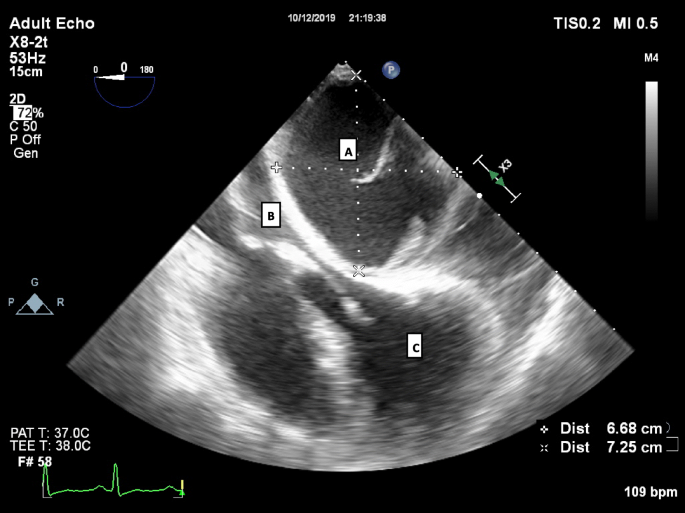

The patient was taken straight to theatre and the transoesophageal echocardiogram confirmed a large (6.68 × 7.25 cm) loculated posterior pericardial effusion which at this point was entirely compressing the left atrium. An emergency sternotomy was performed, a large posterior loculated effusion was found which was made up of old venous blood, 450 ml was drained and a pericardial drain placed. The patient’s cardiac output immediately improved and norepinephrine requirement decreased. The pleura was opened bilaterally with straw coloured fluid drained 500 ml on the left and 300 ml on the right, drains were placed bilaterally.